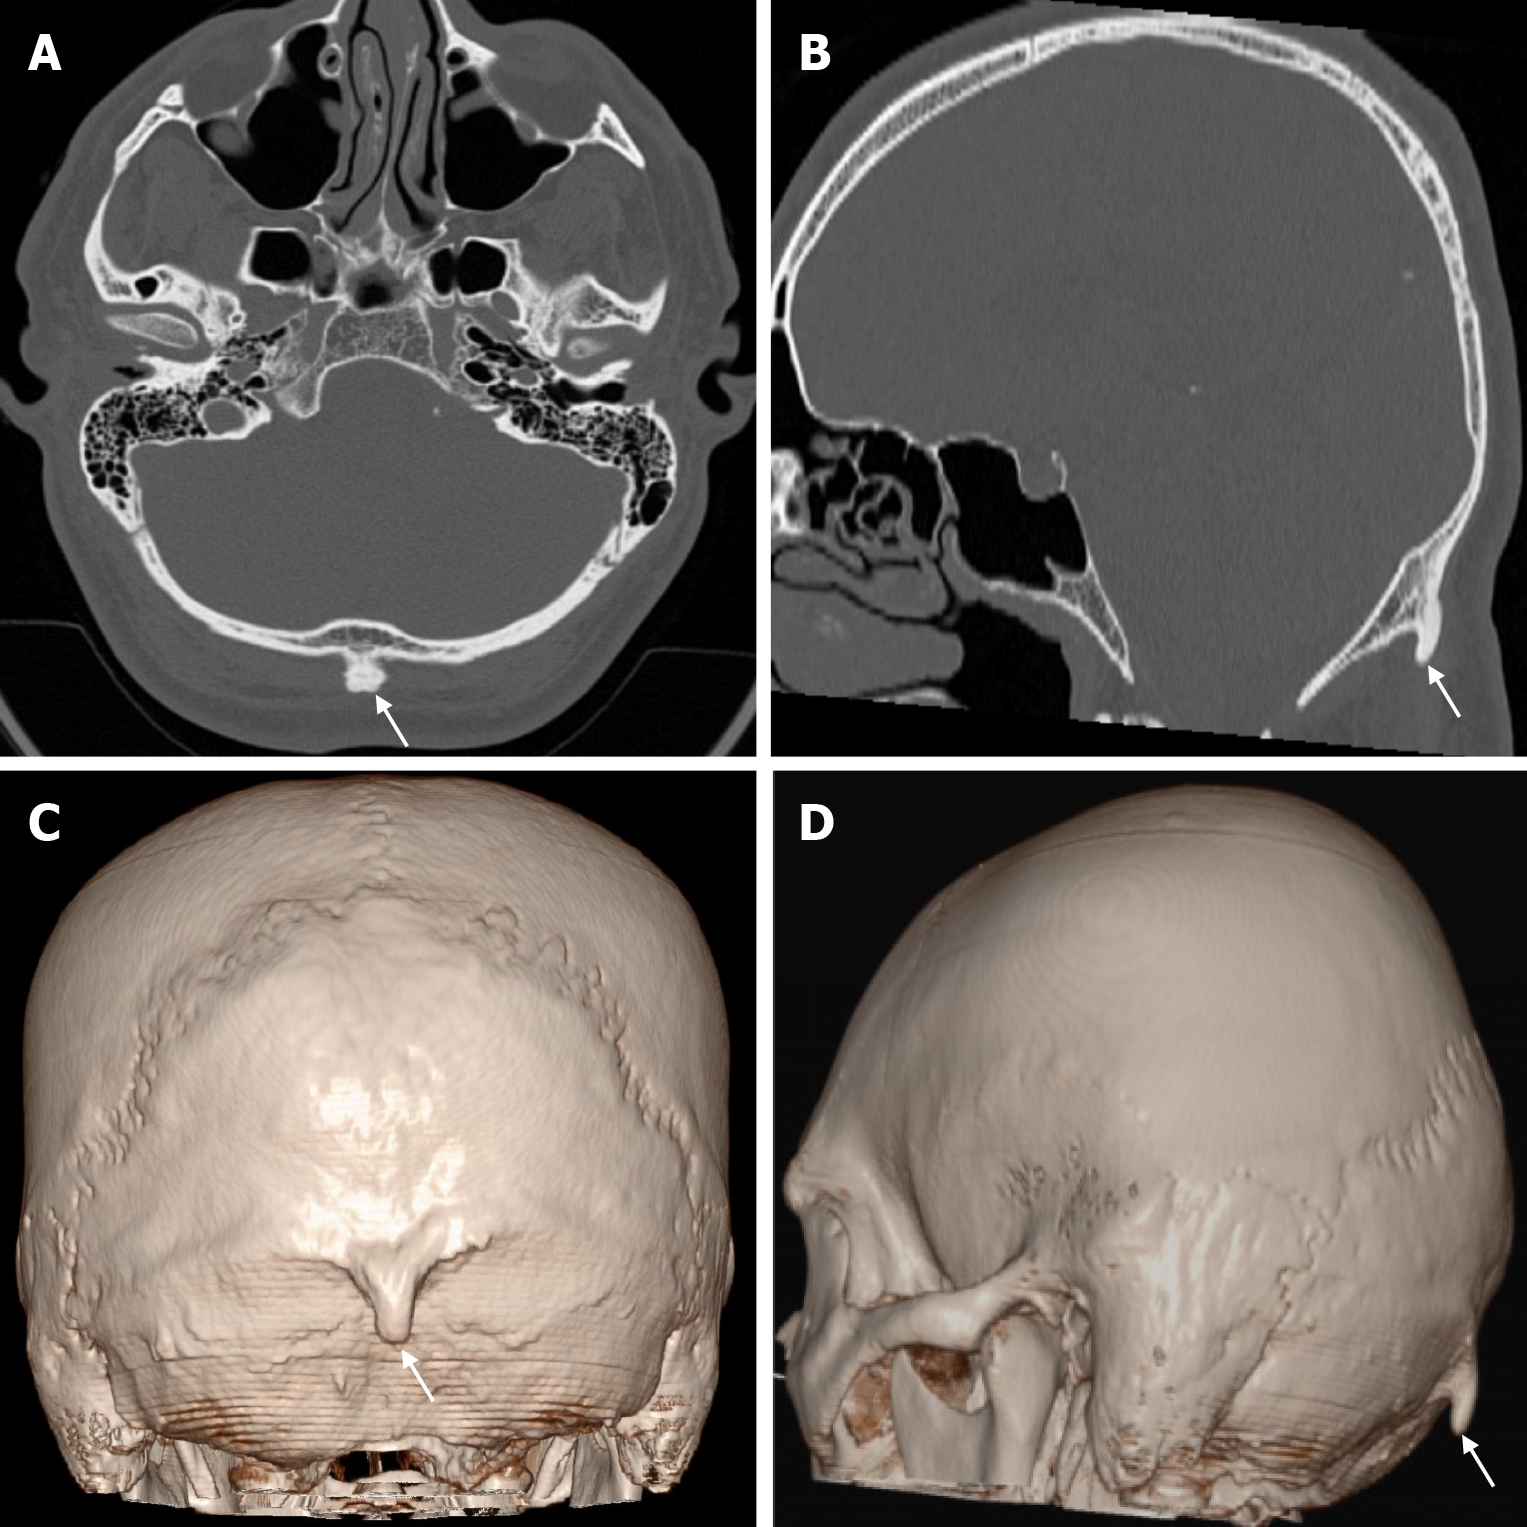

Atretic encephalocele is a midline scalp mass covered by skin containing meninges and neural remnants and/or degenerated brain tissue. In atretic encephaloceles, the brain tissue in the scalp degenerates and may remain attached to the dura mater by a fibrous stalk intracranially. Atretic cephaloceles may be associated with a persistent falcine vein characterized by a vertical embryonic position of the straight sinüs (Figure 6). Most atretic encephaloceles are parietal in location. On CT imaging, a subgaleal soft tissue mass may be seen in a “spinning top” configuration. CT imaging helps visualize bone defects, while MRI helps determine the contents of the encephalocele[3]. The lesions most commonly confused with atretic encephaloceles are sinus pericranii and dermoid cysts[25].